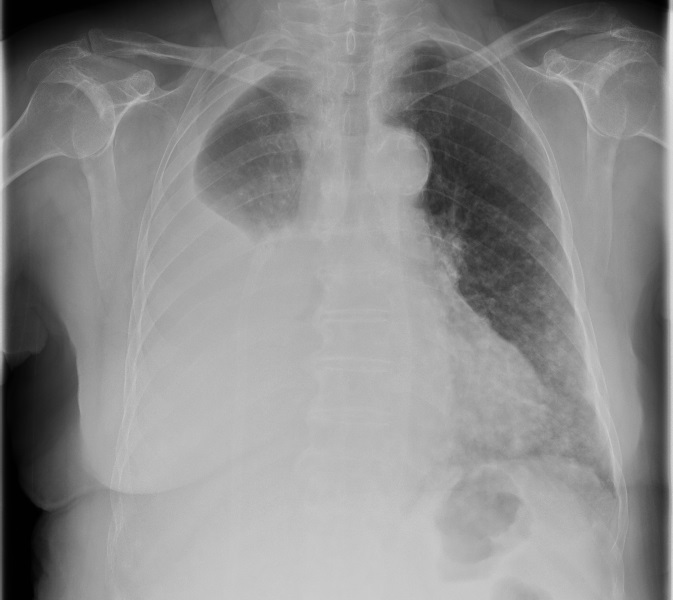

Mme K. est admise aux urgences pour exploration d’une douleur thoracique. Cette femme de 76 ans est suivie en cardiologie depuis dix ans pour un rétrécissement aortique, une hypertension artérielle (HTA) et une dyslipidémie. Elle est parfaitement autonome à domicile. Elle fume un demi-paquet de cigarettes par jour depuis trente ans. Elle est traitée par rivaroxaban (anti-Xa) depuis six semaines pour une thrombose veineuse profonde (TVP) du membre inférieur droit survenue à l’occasion d’un voyage en voiture. Le reste de son traitement comporte de la simvastatine et de l’hydrochlorothiazide.

Depuis trois jours, elle présente une douleur thoracique croissante, latéralisée à droite et survenue sans facteur déclenchant évident.

Question 1 - Parmi les propositions suivantes, quels diagnostics vous semblent compatibles avec ce tableau clinique ?